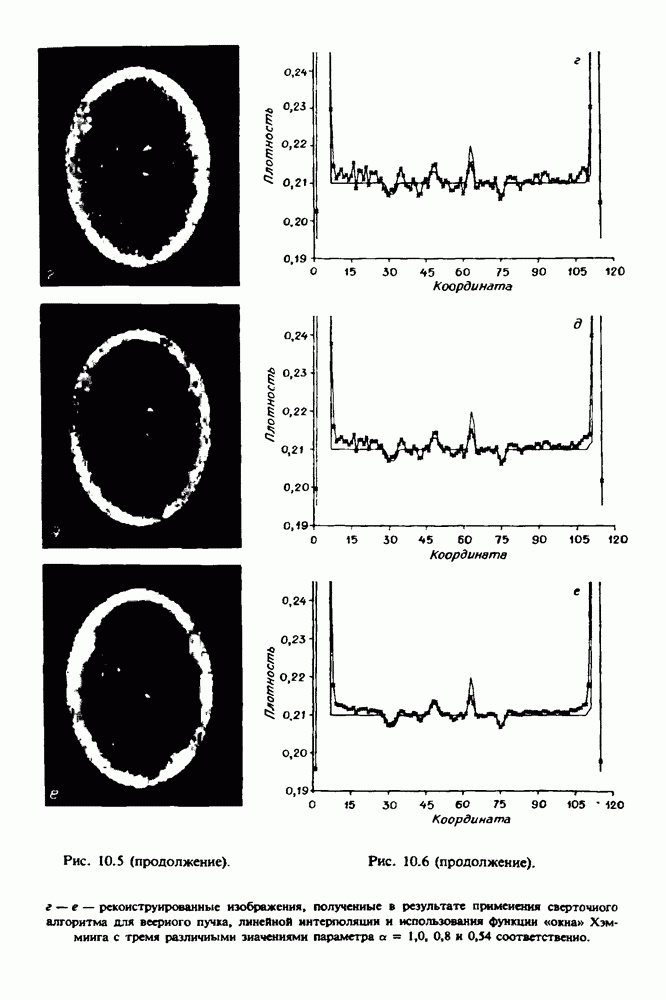

15.5. ЭКСПЕРИМЕНТАЛЬНЫЕ РЕЗУЛЬТАТЫ

Наш первый пример относится к случаю отображения системы желудочков головного мозга человека, которое было сделано по восьми смежным срезам толщиной На рис. 15.1 (вверху) приведены фрагменты из 80 х 80 элементов изображения трех из указанных срезов. Система желудочков изображена на фрагментах полностью. Размер элемента изображения в срезах составлял 1,5 х 1,5 мм, что соответствовало размеру элементарного

объема 1,5 х 1,5 х 8 мм, хотя более желательна, как и в предыдущих разделах, была бы кубическая форма элементарных объемов. Чтобы преобразовать элементарные объемы в кубические, использовалась линейная интерполяция данных для оценки 38 смежных срезов толщиной 1,5 мм. Таким образом, формируется массив из 80 х 80 х 32 чисел, характеризующих среднюю плотность множества элементарных объемов кубической формы.

Причина, по которой желудочки мозга выглядят более темными, чем окружающие ткани, состоит в том, что они содержат спинномозговую жидкость с несколько меньшим, чем у мозга, линейным коэффициентом ослабления (табл. 4.1). Поэтому диапазон значений, введенный в разд. 15.1, оказался таким, что его верхний предел стал больше, чем линейный коэффициент ослабления цереброспинальной жидкости, но меньшим, чем для самого мозга. Последнее означает, что все элементарные объемы, характеризующие спинномозговую жидкость, имеют числа Хаунсфилда в указанном диапазоне Таким образом, множество элементарных объемов, в которых числа Хаунсфилда лежат в диапазоне (разд. 15.2), содержит не только области желудочков, но также и другие части мозга, либо заполненные спинномозговой жидкостью, либо не заполненные ей, но имеющие по разным причинам такие же числа Хаунсфилда в данном диапазоне, например, вследствие наличия шума в исходных данных, артефактов при реконструкции и т.д. Элементарные объемы, которые принадлежат множеству изображены в виде светлых областей в нижней части рис. 15.1. Анатомическая картина соответствующих частей системы желудочков, показывающая в том числе положение corpora quadragemina («четверохолмие»), приведена на рис. 15.6.

Рис. 15.6. Анатомическая структура фрагмента системы желудочков головного мозга человека. 1 — передние рога латерального желудочка; 2 — третий желудочек; 3 — четверохолмие; 4 — задние рога латерального желудочка.

Рис. 15.7. (см. скан) Трехмерные проекции зарегистрированной поверхности системы желудочков головного мозга человека.

Для формирования трехмерного изображения системы желудочков (рис. 15.7) были использованы все рассмотренные в трех предыдущих разделах операции определения границ органов, исключения скрытых их частей поверхности и наложения теней. Число зарегистрированных граничных граней для системы желудочков составляло 8970, при этом регистрация множества из 80 х 80 х 38 элементарных объемов требует менее 0,5 мин машинного времени (на мини-ЭВМ типа Eclipse S/200).